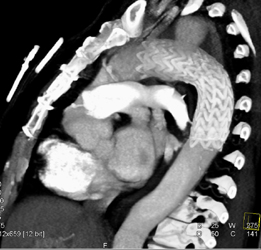

Renal Artery Aneurysm in Multiple Views